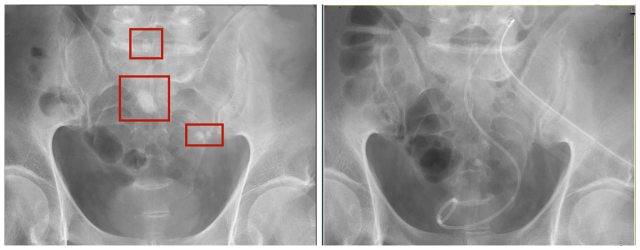

术前红框为结石主体存在区域,术后影像显示结石清除干净

尽管“软硬兼顾”,但因为患者肾盏的可操作空间非常有限,加上异位肾的的结构复杂,仍然有结石藏在小角度、平行肾盏里。此时,“精细清扫战场”的第四镜登场,通过超声明确残余结石位置,李建兴使用其发明的、拥有自主知识产权的“针状肾镜”——直径只有1.3毫米,通过实时传回的高清影像,再次建立直达结石的穿刺通道,利用激光碎石。最终这例复杂的泌尿系结石微创手术耗时两小时顺利完成。碎石数十粒,患者腹部仅有两个直径1厘米的创口和一个针眼。